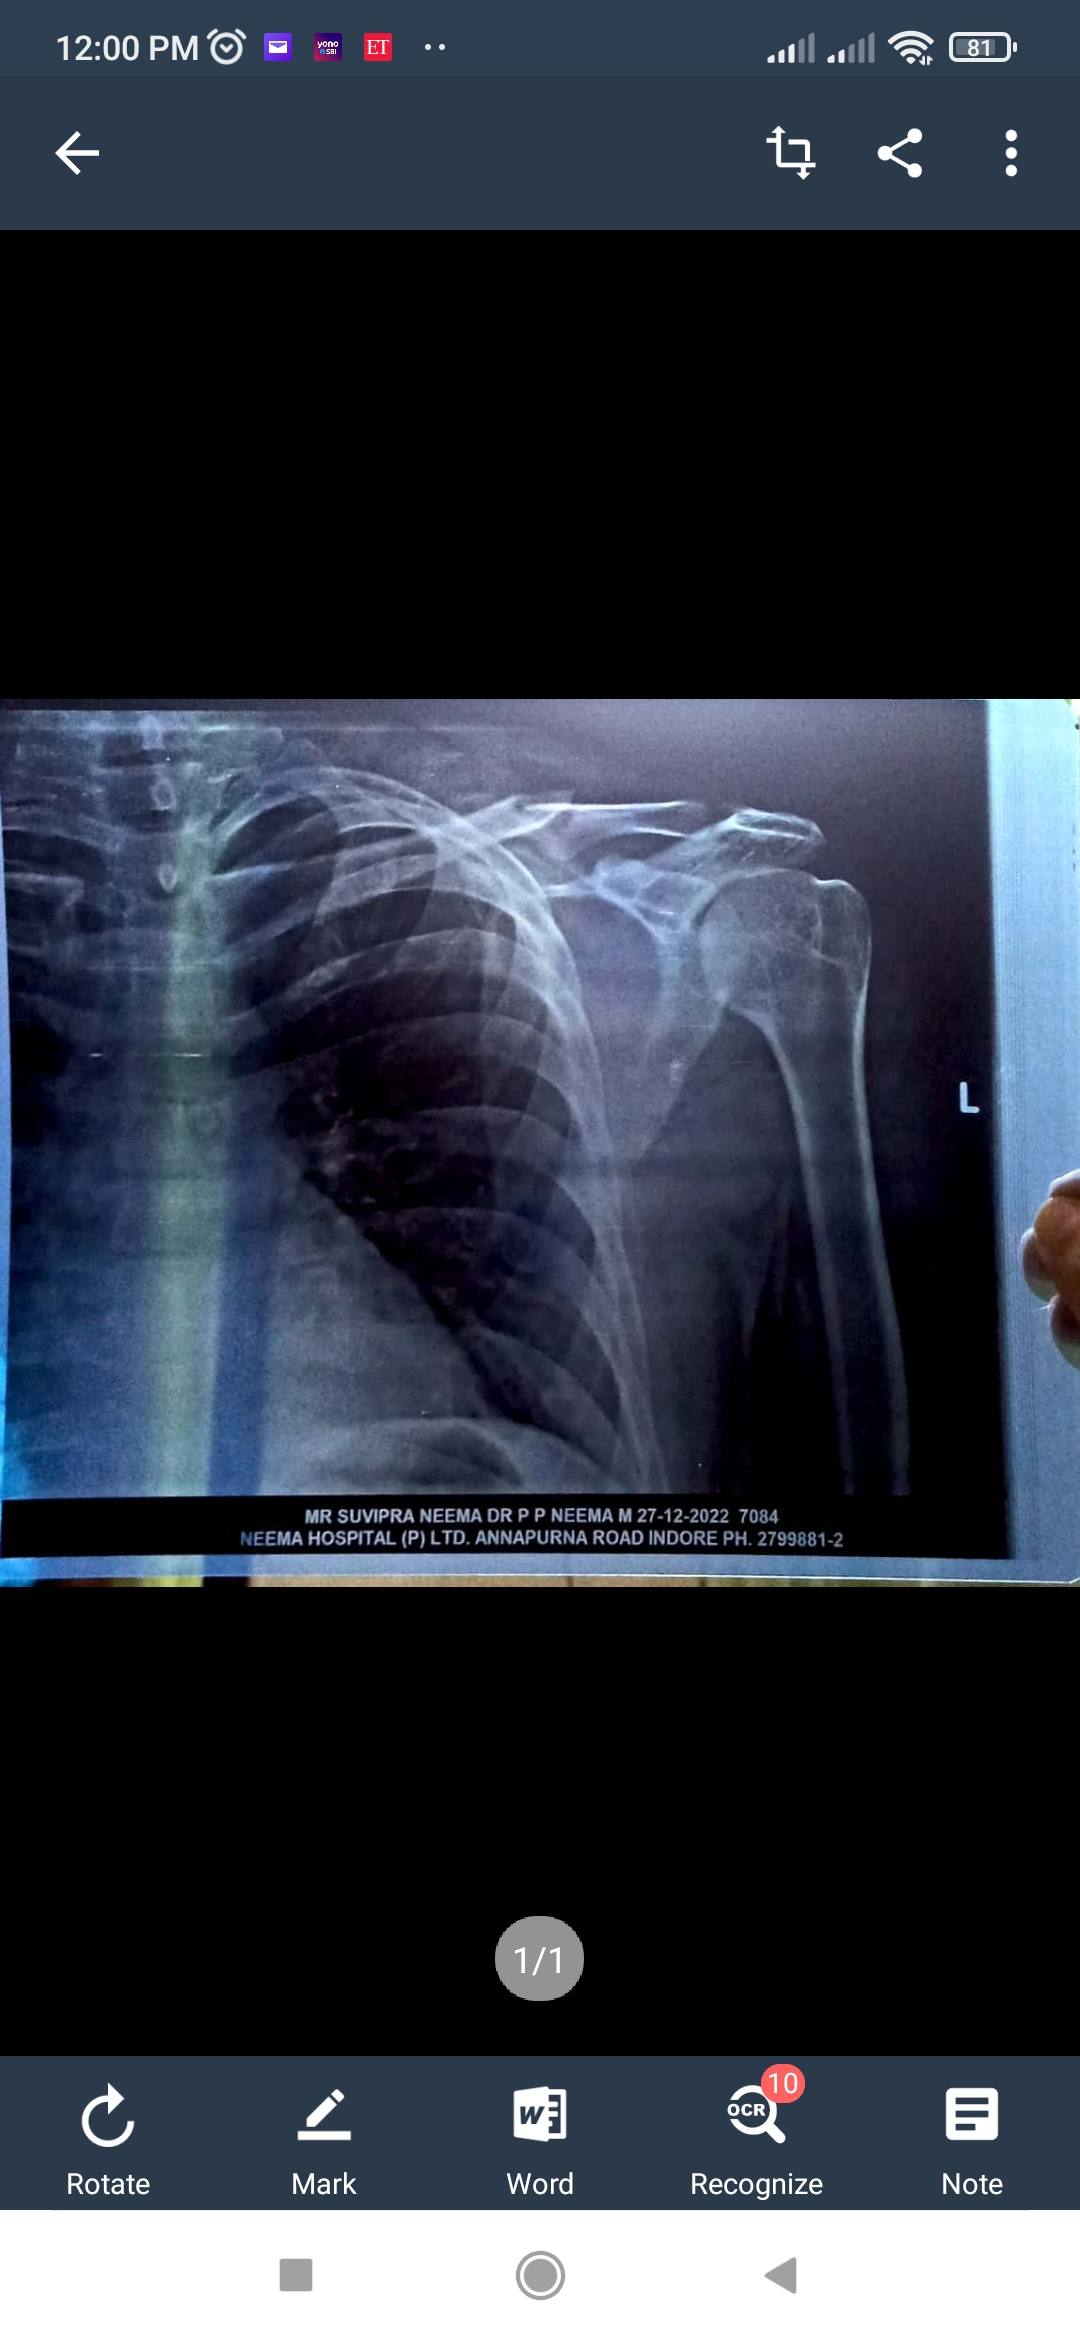

ye apne aap jud jayega bas isme 3 mahina lagega